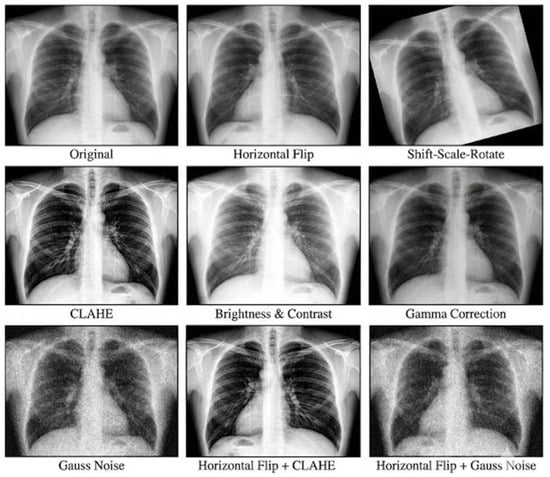

Decision-Aware Vision Mamba with Context-Guided Slot Mixing for Chest X-Ray Screening and Culture-Based Hierarchical Tuberculosis Classification

by Wangsu Jeon, Hyeonung Jang, Hongchang Lee, Chanho Park, Jiwon Lyu and Seongjun Choi

Sensors 2026, 26(7), 2100; https://doi.org/10.3390/s26072100 - 27 Mar 2026

Distinguishing Active from Inactive Tuberculosis (TB) on Chest X-rays presents a clinical challenge due to overlapping radiological signs. This study introduces Vision Mamba CGSM, a deep learning framework integrating a State Space Model (SSM) backbone with a Context-Guided Slot Mixing (CGSM) module. The [...] Read more.

Distinguishing Active from Inactive Tuberculosis (TB) on Chest X-rays presents a clinical challenge due to overlapping radiological signs. This study introduces Vision Mamba CGSM, a deep learning framework integrating a State Space Model (SSM) backbone with a Context-Guided Slot Mixing (CGSM) module. The SSM captures global anatomical context, while the CGSM module isolates subtle pathological features by applying localized spatial attention. We validated the model using a hierarchical diagnostic scheme covering Normal, Pneumonia, Active TB, and Inactive TB. Experimental evaluations demonstrate an accuracy of 92.96% and a Youden Index of 79.55% on the independent test set. In the specific binary classification of Active vs. Inactive TB, the model recorded a specificity of 97.04%, outperforming standard baseline architectures including ResNet152 and ViT-B. Additional validations on external datasets confirm the consistent generalization of the proposed feature extraction mechanism. Full article